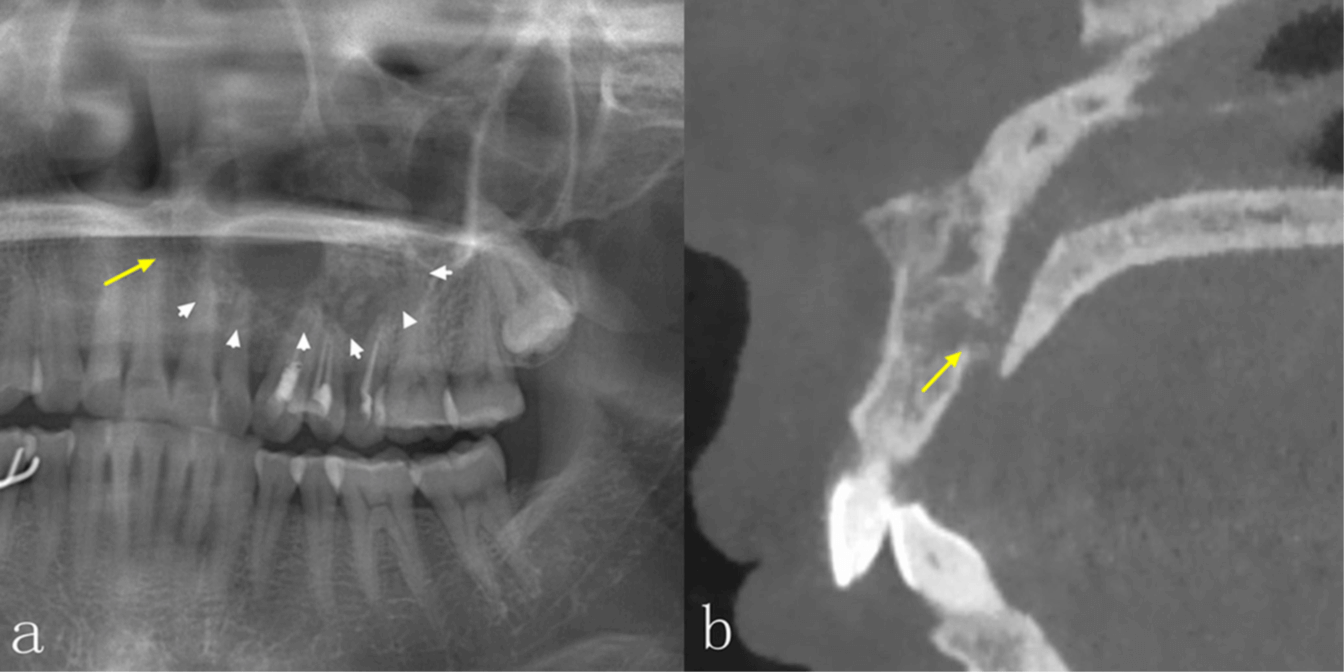

No obstante, la TCCB también tiene sus desventajas. Por ejemplo, la TCCB es propensa a diversos artefactos, especialmente artefactos metálicos y de movimiento, que pueden tener un efecto perjudicial sobre la calidad de la imagen. En comparación con la tomografía computarizada espiral (tomografía medica), su resolución de contraste es menor y los tejidos blandos se visualizan con menor calidad. La dosis de radiación y el coste son también factores importantes que deben tenerse en cuenta a la hora de tomar decisiones clínicas. La dosis depende principalmente del tipo de equipo y de los ajustes de exposición, incluyendo el campo de visión, el tiempo de exposición, la corriente del tubo (mA) y la energía/potencial (kV).6 En comparación con la PAN, la dosis efectiva de radiación de la TCCB suele ser significativamente mayor, lo que debe tenerse en cuenta cuando se requiere la obtención de imágenes. Las diferencias significativas en el aspecto radiológico de las lesiones intraóseas entre la PAN y la TCCB se encuentran en la integridad de los bordes corticales, la expansión de los límites anatómicos circundantes, el adelgazamiento cortical, la destrucción cortical y la reabsorción radicular, especialmente en las regiones anteriores de ambos maxilares y en el maxilar superior. La TCCB también mejora la precisión diagnóstica, especialmente en las lesiones del maxilar superior.

La TCCB proporciona información más completa y detallada, lo que resulta útil para realizar el diagnóstico. Aunque la precisión diagnóstica estaba estrechamente relacionada con la experiencia de los médicos, la discrepancia entre los dos estudios se atribuye muy probablemente al mayor tamaño de la muestra de nuestro estudio. La TCCB fue precisa a la hora de mostrar las características de las lesiones, como la ubicación, la localización, la densidad interna, la expansión y su efecto sobre las estructuras circundantes, lo cual es de ayuda a los odontólogos a realizar un diagnóstico más preciso.